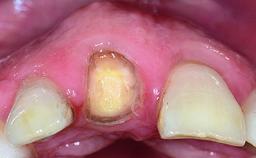

A 36-year-old male patient with a compromised maxillary central incisor was referred by his general dentist for consultation. The patient’s chief complaints were the gradual debonding of a temporary crown on the right central incisor and unsatisfactory esthetics due to an increasing diastema between the right central and lateral incisors. The patient reported a traumatic event some years previously, when a crown had been placed after root-canal treatment. The referring dentist wanted to provide a new crown restoration, but was concerned about the condition of the residual root. Anamnesis was negative for any other dental or periodontal pathology in the remaining dentition. The patient reported taking no medications: He was a smoker (10 to 15 cigs/day) and had realistic esthetic expectations.

Bone Volume Deficient horizontally, requiring prior grafting